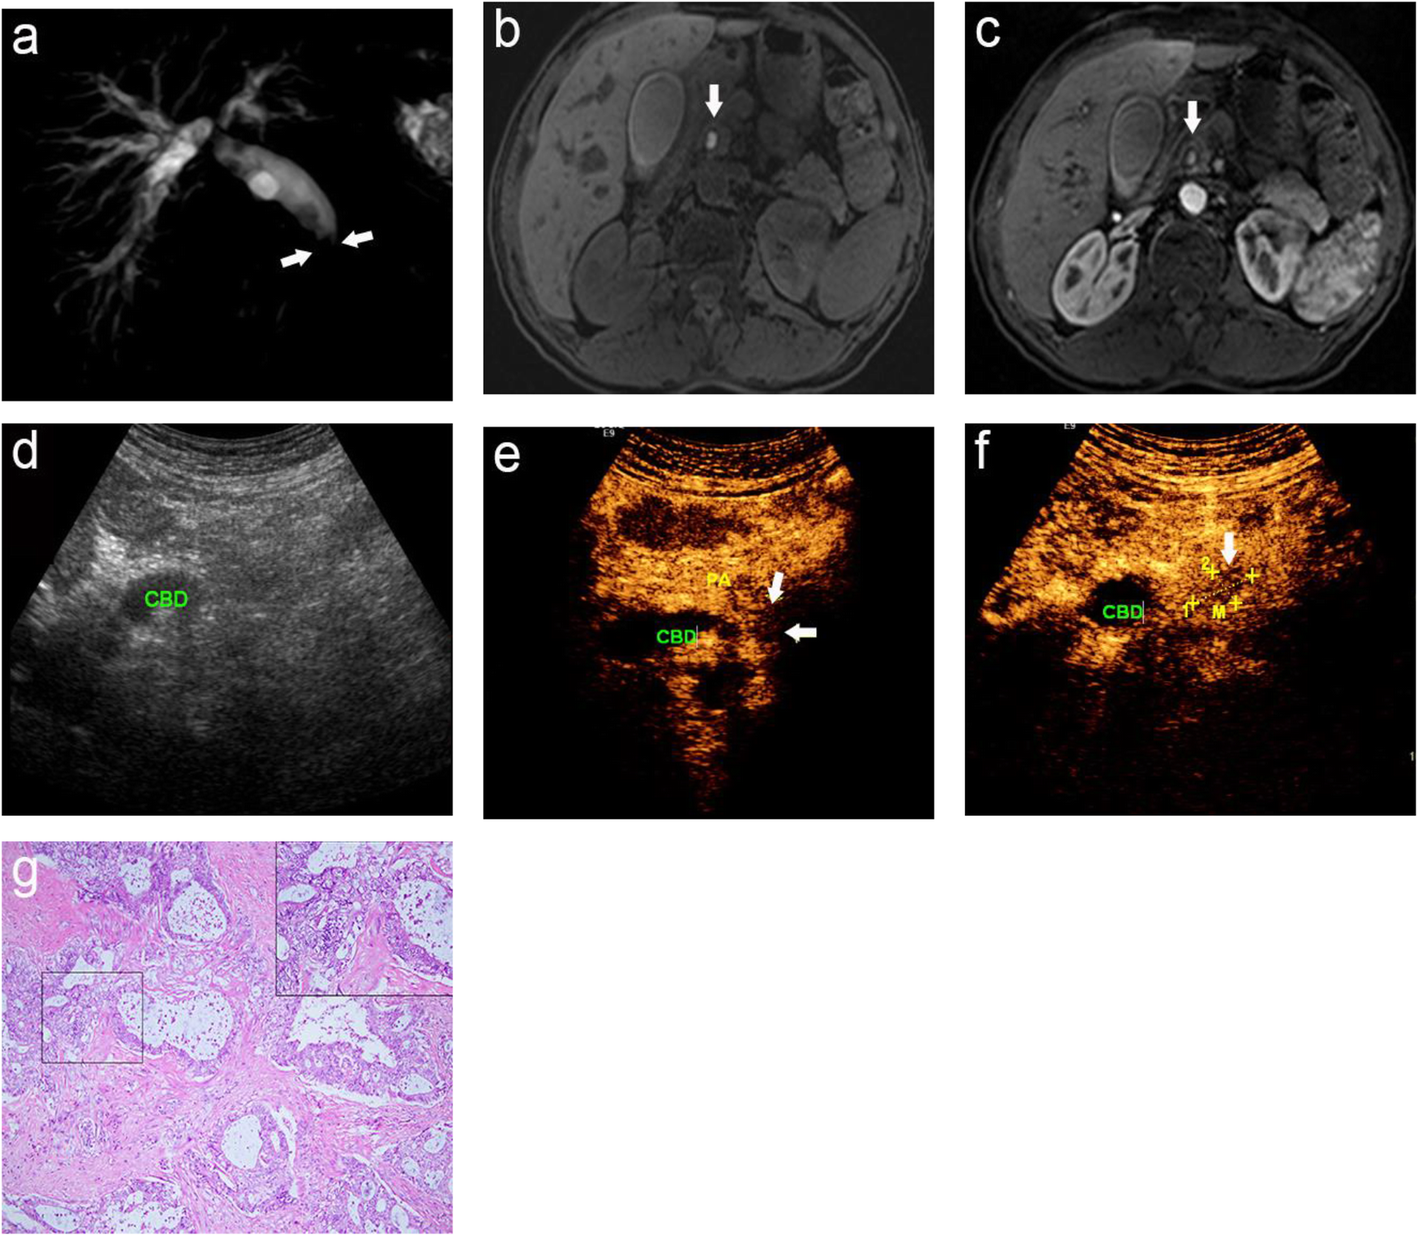

Fig. 1

A 58-year-old male was misdiagnosed as having a common bile duct stone by MRI, which was pathologically-confirmed as choledochal adenocarcinoma; (a) MRCP image displays the narrowing (arrow) of the distal CBD suddenly and the expansion of the biliary tract; (b) Axial T1-weighted images and (c) T1-weighted DCE-MRI show high signal nodules in the CBD, and the possibility of stones was considered (arrow), yet no enhancement is seen in the structure of bile duct wall; (d) CUS shows dilated CBD; (e, f) CEUS shows a cauliflower-like mass with uneven enhancement (arrow), which should be considered for common bile duct carcinomas; (g) Histopathological examination reveals that some malignant glands infiltrated into the bile duct wall. CBD: common bile duct; PA: pancreas